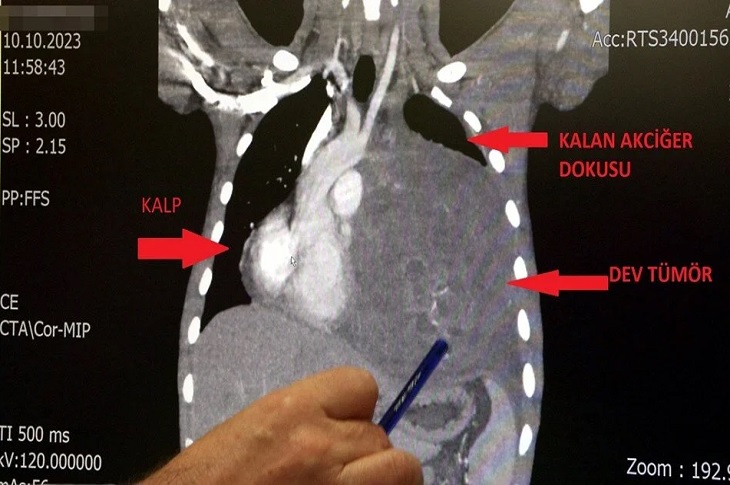

İstanbul’da Doktorları Bile Şaşırtan Vaka: Kalbi 12 Santim Sağa Kaydı

İstanbul’da yaşayan 21 yaşındaki Burak Aktaş, Ağustos ayında halsizlik ve nefes darlığı şikayeti ile doktora gidince sol göğüs boşluğunda portakal…